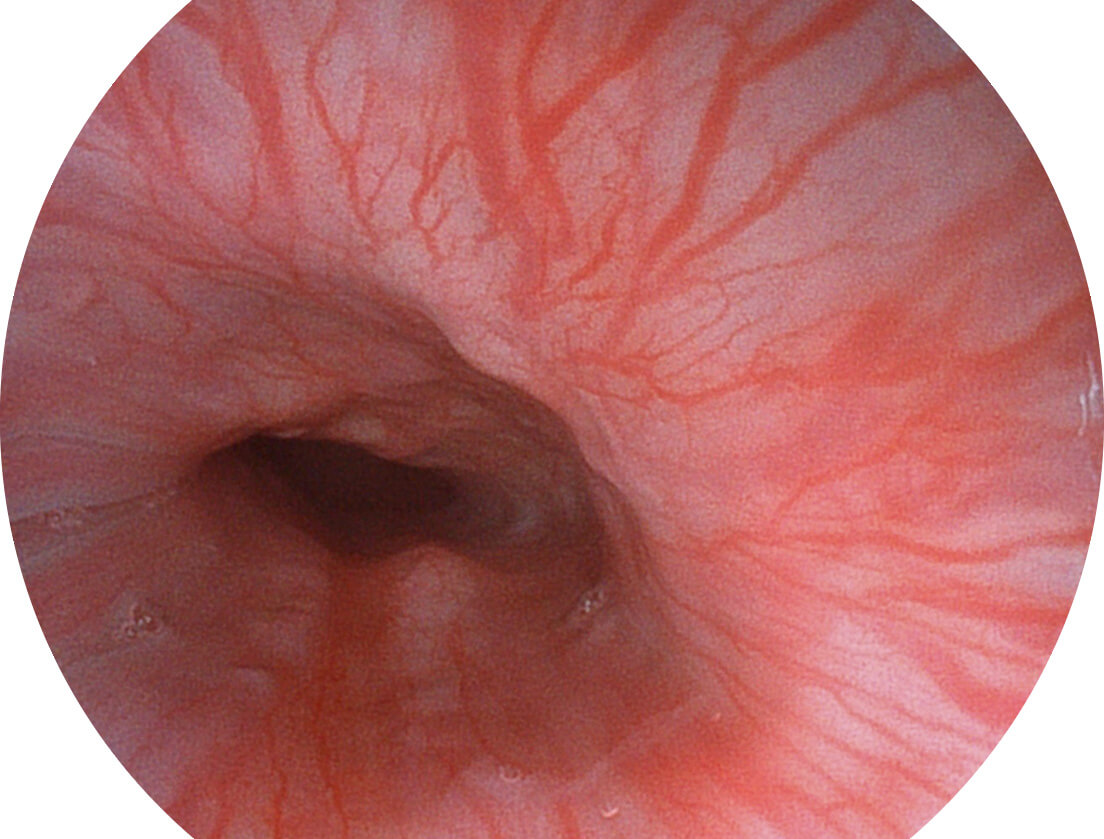

白光图像

SFI图像

图像具有高亮度、高黏膜血管颜色对比度的特点,且不改变粘液、食物残渣、粪便的基本颜色,可在中远景下进行观察,助力消化道早期疾病的诊断。

采用光路合束技术,光谱自由度高,实现了更丰富的照明模式,染色模式SFI及VIST,从远景到近景,助力消化道早期疾病诊断。